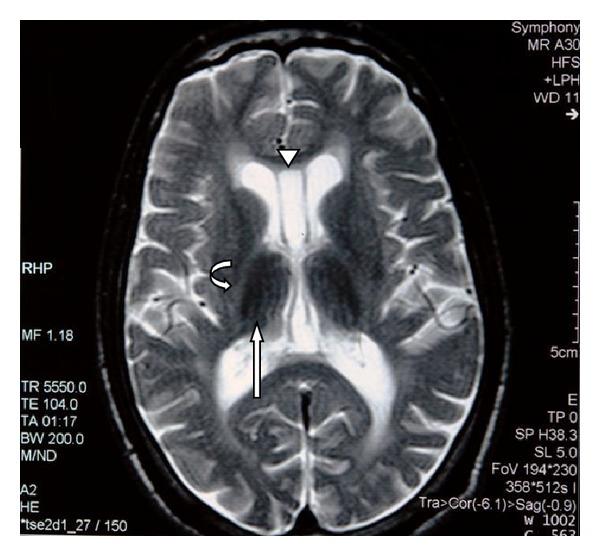

A 29-year-old male petrol station pump attendant was admitted with ataxia and clinical evidence of a sensorimotor polyneuropathy which developed over the preceding 3 months. He had cognitive dysfunction, hearing loss, and cerebellar clinical abnormalities that came on slowly over the three years. He had a fifteen-year history of sniffing mostly glue, occasionally paint thinners, and, in the recent two years, gasoline. Magnetic resonance brain imaging showed abnormalities of the cerebral cortex, cerebral white matter, corpus callosum, hippocampus, brainstem and cerebellar atrophy, hypointensities of basal ganglia, red nuclei, and substantia nigra as previously described in toluene sniffing. Abstinence for six months led to partial clinical improvement. Clinicians need to be aware of this preventable entity which has peculiar radiological findings which are being increasingly accepted as typical.

一名29岁的男性加油站油泵服务员因共济失调以及在前3个月内出现的感觉运动性多神经病的临床证据而入院。他有认知功能障碍、听力丧失和小脑临床异常,这些症状在3年里逐渐出现。他有15年的吸入史,主要是胶水,偶尔是油漆稀释剂,近两年来还吸入汽油。磁共振脑成像显示大脑皮质、脑白质、胼胝体、海马体、脑干和小脑萎缩,基底神经节、红核和黑质低信号,正如先前在甲苯吸入中所描述的那样。禁欲6个月导致临床症状部分改善。临床医生需要意识到这种可预防的疾病,它有独特的放射学表现,并且越来越被认为是典型的。